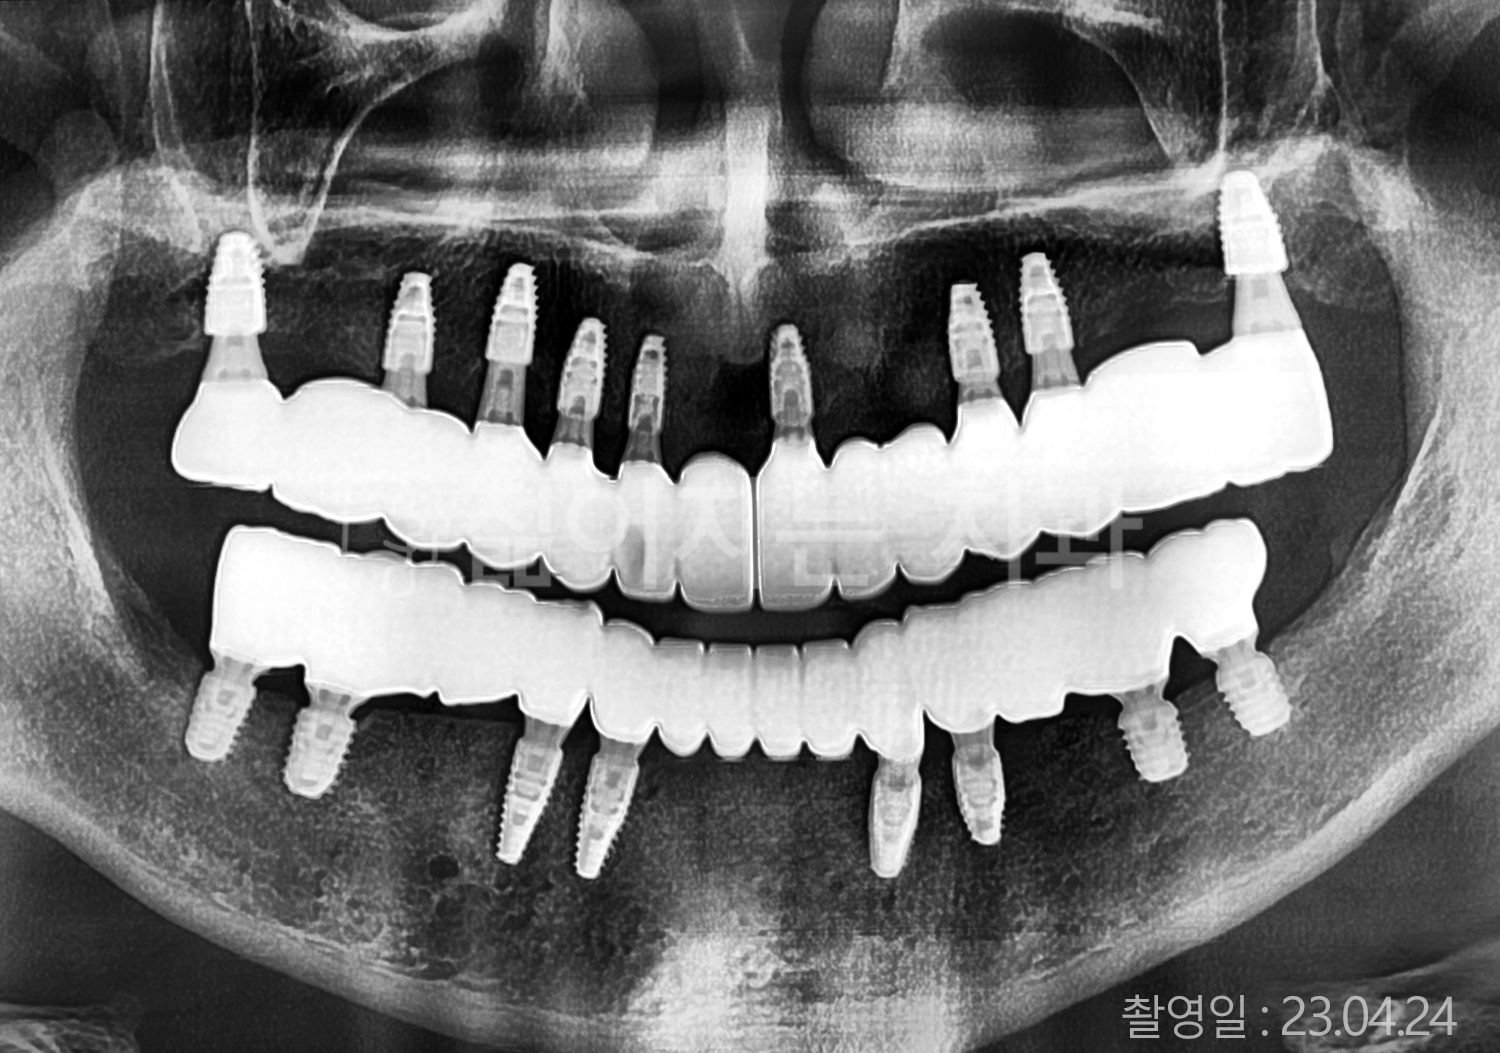

• 50대 전체치아 10개 이상 임플란트